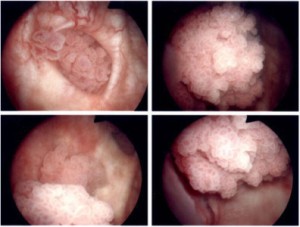

| Tumor Kandung Kencing |

Tumor kandung kencing merupakan keganasan saluran kencing terbanyak kedua setelah tumor prostat. Tumor ini menyerang pria 2 kali lebih banyak dibandingkan wanita. Di daerah industri kejadian tumor ini meningkat tajam. Perokok mempunyai resiko 2 – 6 kali lebih tinggi menderita tumor kandung kencing dibandingkan yang bukan perokok. Kebiasaan mengkonsumsi kopi dan pemanis buatan diduga meningkatkan resiko timbulnya tumor kandung kencing. Infeksi saluran kemih berulang beresiko besar menjadi tumor kandung kencing terutama akibat zat karsinogen (pencetus tumor) yang dihasilkan bakteri E. coli dan Proteus spp. Seseorang perlu mewaspadai dirinya menderita tumor kandung kencing apabila mengeluh adanya darah di dalam air kencing yang kejadiannya berulang (kambuhan) dan justru tidak disertai rasa nyeri. Meskipun pada beberapa kasus yang sudah lanjut rasa nyeri akan tetap muncul, namun pada stadium awal biasanya tidak nyeri. Seperti gejala pembesaran prostat dimana penderita mengeluh tidak dapat kencing atau kurang lancar dalam berkemih, darah yang menggumpal pada kasus tumor kandung kencing dapat mengakibatkan keluhan yang sama karena gumpalan darah tersebut menghambat keluarnya air kencing. Terapi untuk tumor kandung kencing yang pertama kali dilakukan adalah tindakan reseksi (pengerokan) kandung kencing menggunakan alat yang dimasukkan melalui saluran kencing. Setelah itu tergantung hasil evaluasi, terapi selanjutnya dapat berupa instilasi (memasukkan zat sitostatika melalui kateter) ke dalam kandung kencing, radiasi, kemoterapi dan sistektomi (pengangkatan kandung kencing).